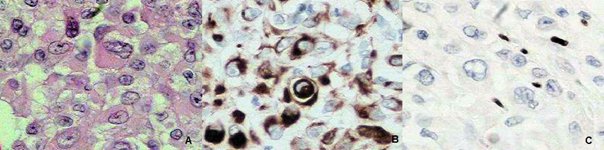

A 21-year-old man with pancreatic neoplasm was referred to Specialized Oncology Therapy Center of Santa Casa de Misericórdia de Rondonópolis Hospital. Surgical history: The patient informed that it was submitted to surgical procedures (partial pancreatomy and gastrectomy, splenectomy and retroperitoneal lymphadenectomy). Anatomopathological analyses revealed pancreatic malignant invasive neoplasm, with poor differentiated cells, necrotic lesion, with angiolymphatic infiltrate, although no peritoneal infiltrate was detected. As a rare neoplasm case, the Department of Pathology from Emory University (Atlanta, USA) was contacted and confirmatory exams indicated malignant epithelioid neoplasm. Immunohistochemistry of pancreatic tissue (Figure 1) indicated cells with rhabdoid features, positive results for cytokeratins and negative results for INI-1 and other markers, such as SMARCB1. Thus, diagnosis suggested high-grade malignant epithelioid neoplasm, compatible with extra renal MRT. Patient was submitted to image exams (abdominal and pelvic CT scan) that demonstrated the presence of multiple nodules and mass with liquefied and necrotic center in both hepatic lobes. Systemic chemotherapy scheme was initiated with ifosfamide, mesna and doxorrubicin. Although after first chemotherapy round patient died because disease complications, such as cachexia, poor general condition and hydro electrolyte disturbance. The patient denied having a relevant family and medical history.

Figure 1 A, Rhabdoid pattern of cells stained with hematoxilin; B, positive results for 40, 48, 50 and 50,6 kDacytokeratins; C, negative result for INI-1 gene product.